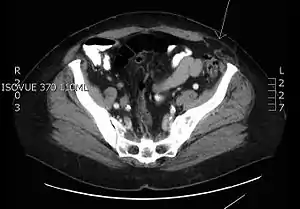

O diagnóstico é clínico. A herniação, em caso de dúvida, pode ser identificada com tomografia computadorizada ou ultrassonografia.[5]